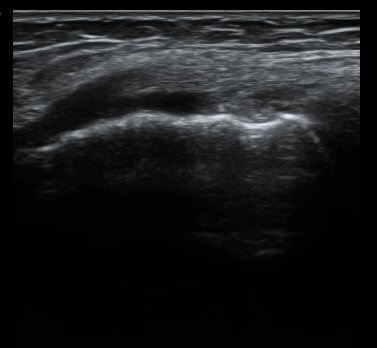

¹«¸­ ³»ÃøºÎÀδë Á¾´Ü¸é°Ë»ç¿¡¼­ ³»ÃøºÎÀδë Ç¥Ãþ±ÙÀ§ºÎ Àú¿¡ÄÚ ºÎÁ¾ ¹× ½ÉÃþ±ÙÀ§ºÎ ºÎºÐÆÄ¿­ÀÌ

°üÂûµÊ(±×¸² 3, 4).